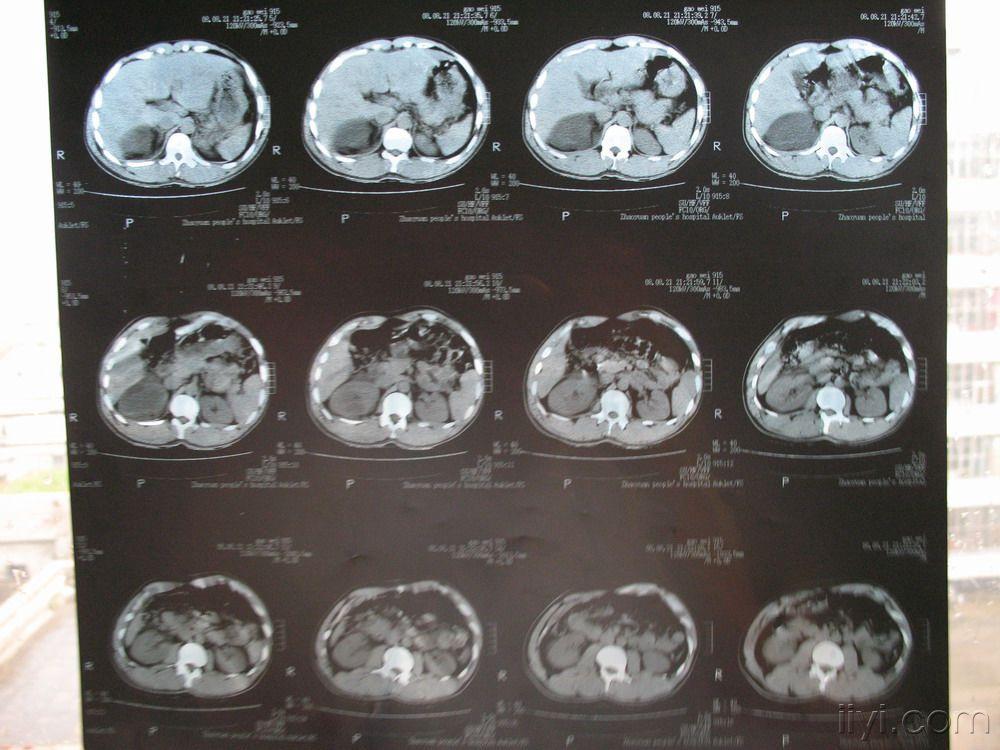

【讨论】肝肾隐窝占位病变鉴别 [病例帖]

讨论外伤后右肝肾隐窝肿物

此断面上肝右后叶与右肾相邻,肝肾之间的腹腔间隙称肝肾隐窝,少量腹水

3 肝肾隐窝积血.jpg